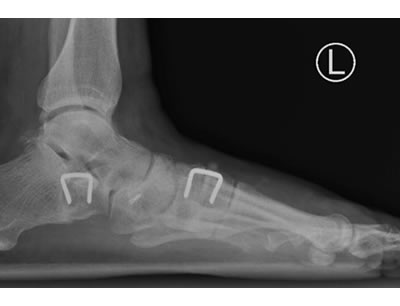

Typical Flatfoot Deformity

Non Arthritic Flatfoot Deformity

Correction of Deformity with Tendon Augmentation/transfer and Bone Grafting